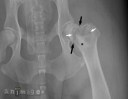

RadioQuiz 19 – Réponse

RadioQuiz 14 – Réponse